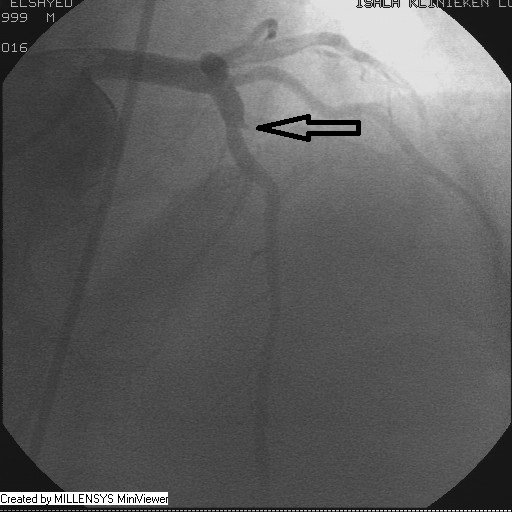

Patient transfered to Cardiac Catheterization Laboratory, coronary angiography showed atherosclerotic coronaries but without significant lesions, especially LAD that was patent with TIMI 3 flow (Figure 1- 5). Re-evaluation of the Angiography showed a small stump that can be for an occluded 1st diagonal (Figure 2a), at that level the LAD has a non-significant lesion.

After crossing with the PTCA wire, a minimal flow started to appear in the diagonal branch (Figure 6), then LAD was wired, then a 2x15mm Balloon was used to pre-dilate (Figure 7,8), a big diagonal branch appeared with proximal thrombotic tight lesion (Figure 9), the diagonal angle to LAD was about 90 degree (Figure 10), so provisional stenting done to diagonal from its ostium with 3x20mm PROMUS ELEMENT PLUS DES (Figure 11,12), with good final result (Figures 13&14).